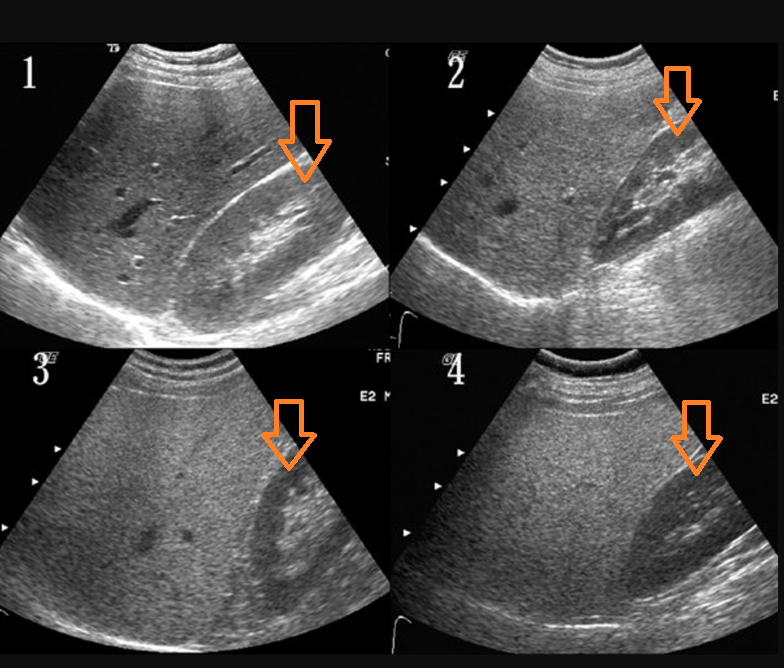

5. 아무리 열심히 일해도 역부족이라서 입고된 재료가 간에 쌓이기 시작하면, 우리가 잘 아는 지방간이 됩니다. (실제로 당뇨약 중에는 지방간의 치료제로 쓰이는 것이 있습니다.)

fattyliverUS.png 갈수록 어두워지는 콩팥, 하지만 실제로는 기름이 끼인 간이 갈수록 밝아지는 것입니다.